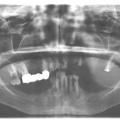

Установка 10 имплантантов на беззубую челюсть с помощью компьютерной программы: Через месяц после удаления

Через месяц после удаления